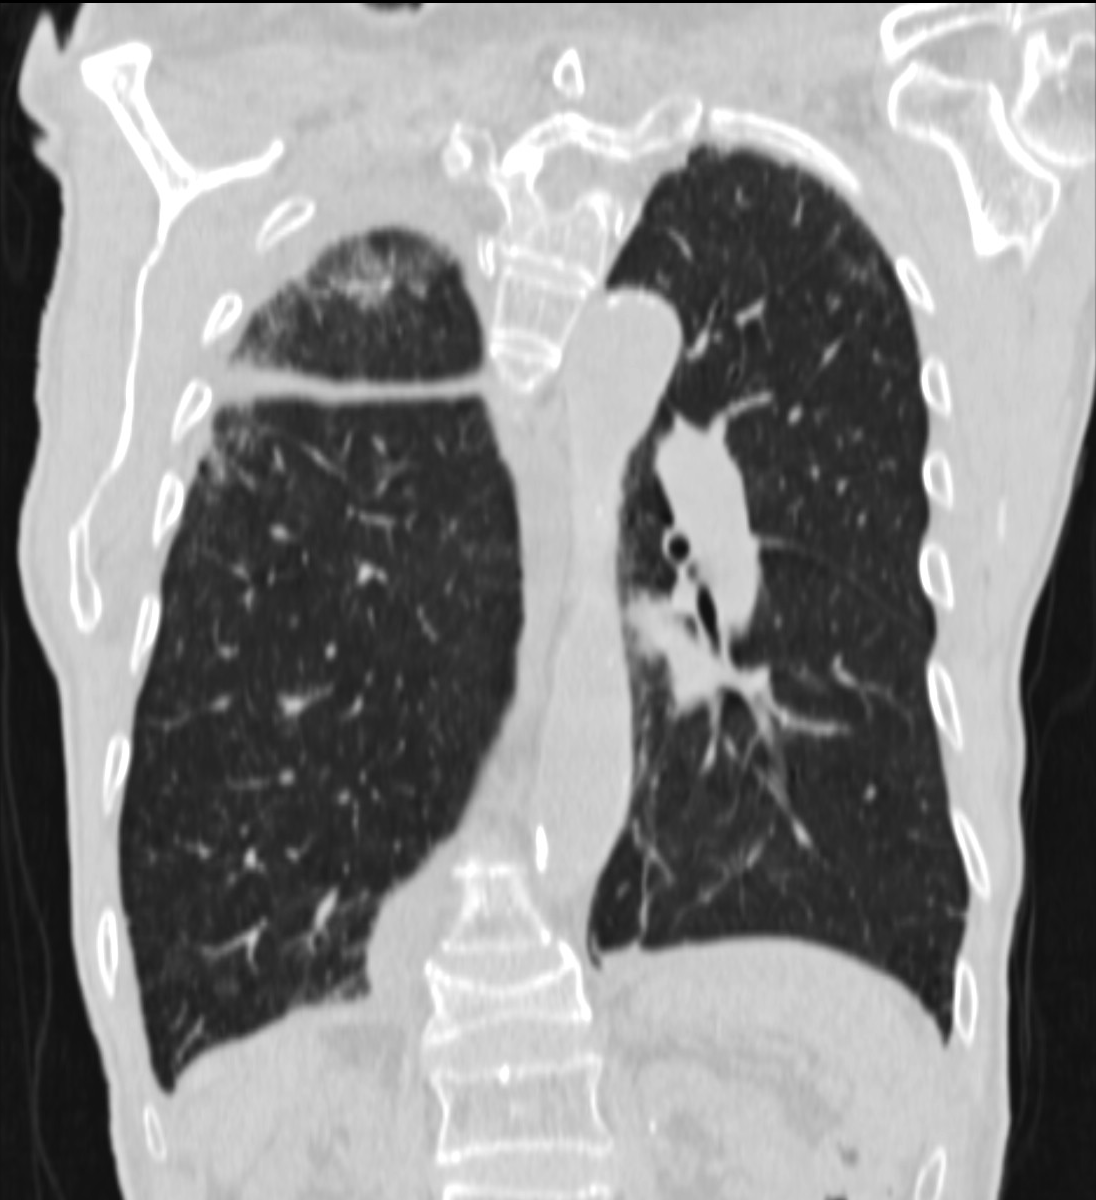

3a: Round shadow: multiple lung metastasis. Chest radiograph (PA)

3b: Multiple lung metastasis, CT lung window (axial, coronal reformat)

3c, coronal reformat

70 year old man, colon tumor.

Radiograph: Bilateral extensive, confluating patchy-nodular shadowing with diffuse reticular pattern. The diaphragm contour is partially blurry bilaterally: lymphangiosis carcinomatosa.

CT: Numerous 1-6 cm round and irregular, lobulated-spiculated contrast enhancing lesions in both lungs, everywhere sporadically.